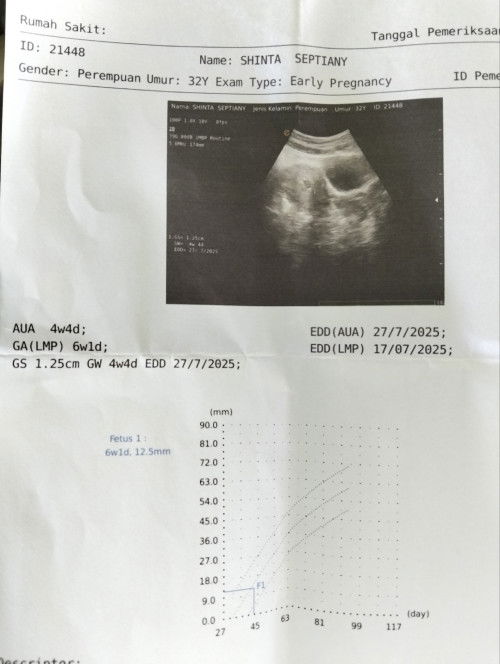

Usia kandungan menurut HPHT 6w tapi di USG kantong kehamilannya baru 4w4d normal gak ya itu?

Jadi ceritanya tadi USG ke puskesmas karena dari awal positif belum periksa ke bidan, nah tadi USG di puskesmas. Pas di USG sudah terlihat kantung kehamilannya, tapi menurut dokternya dilihat dari ukuran kantung nya masih 4w4d. Sedangkan kalo hitungan HPHT harusnya udah 6w. Trus kata dokternya tidak sesuai dengan usia HPHT nya gitu. Jadi kepikiran ada sedih juga, kira kira kenapa ya?